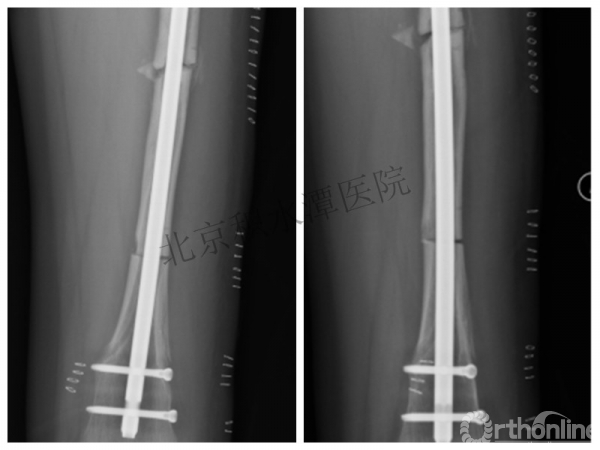

病例分享六

7岁、男孩,桡骨远端骨折

原始损伤片

手法整复后 - 45分钟!

伤后4天复查

伤后30天!

医生的处理方法!——医生终于没有坚持自己的原则!

伤后40天—切开复位内固定!

伤后18个月

手术历时近 5小时!心情之压抑无以言表!因为当时的经治医生是他们的进修生!感觉是他们的失职甚至渎职!

唯一可以肯定—预后不佳!郭教授是党员!是无神论者!但是很诡异的事情:手术中发生—C形臂看不清!拍片条件总是调节不好!手术器械换了三套!内固定钢板总不合适!

术后15月,虽然家长满意了,但是他们医生不满意!